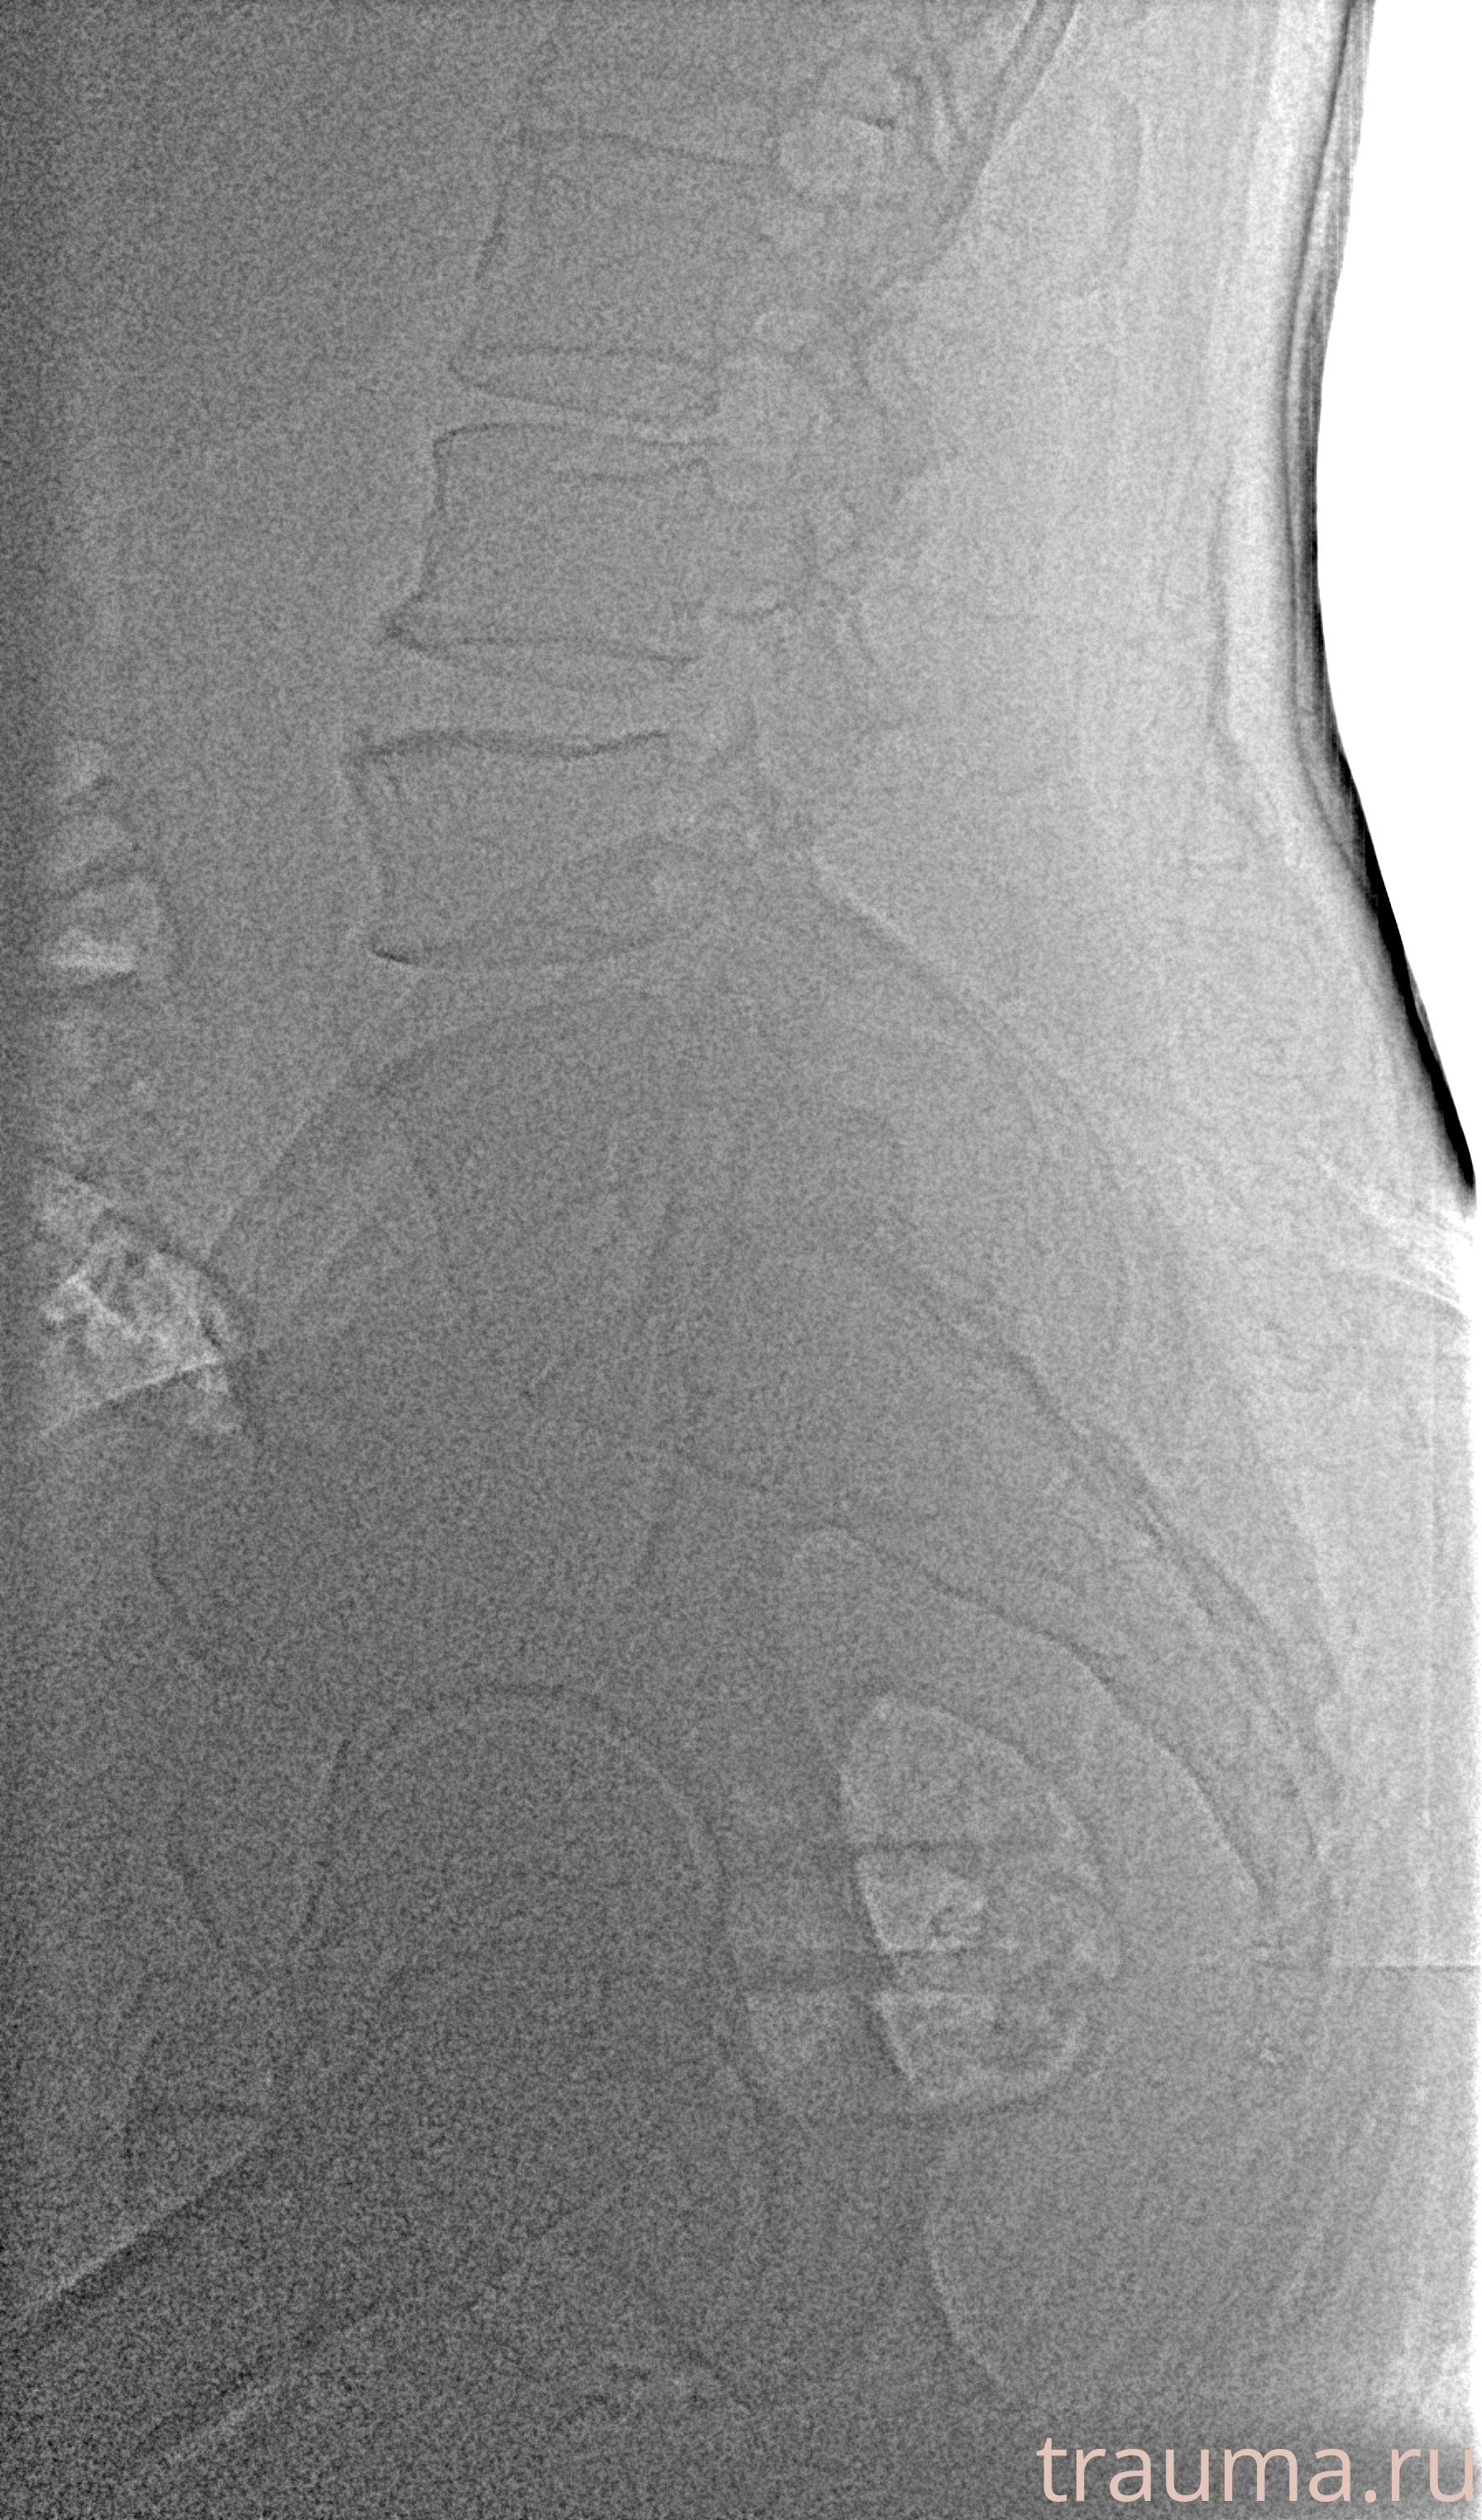

Рентгенограммы

Рентген на дому: по вашему адресу приезжает врач-рентгенолог, травматолог-ортопед с мобильным рентгеновским аппаратом, проводит диагностику травмы или заболевания, делает необходимые рентгенограммы, дает рекомендации по дальнейшему лечению. Получить качественные снимки в домашних условиях возможно благодаря уникальной методике, разработанной МосРентген Центром для института  Склифосовского